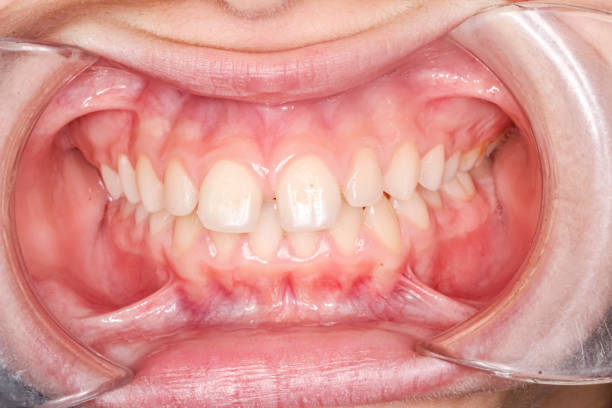

Examen dental que muestra dientes apiñados y mal alineados, un caso típico de maloclusión

Apiñamiento dental. Falta de espacio en la arcada. La maloclusión más común.